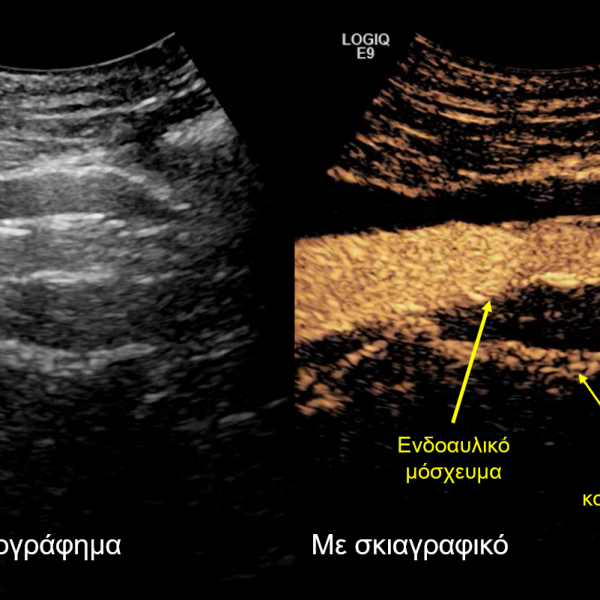

Πρώτη φορά στην Ελλάδα εφαρμόζεται νέα πρωτοποριακή τεχνική για τη θεραπεία υπερνεφρικού ανευρύσματος της αορτής από τον ‘Ομιλο Ιατρικού ΑθηνώνΗ Βενεζουέλα ζήτησε τον επαναπατρισμό του χρυσού της από την τράπεζα της Αγγλίας και η Βρετανία αρνήθηκεΕίχες την τύχη να μεγαλώσεις σαν παιδί;Είκοσι χρόνια Ευρωζώνης και Γερμανός σοφός για θέματα οικονομίας στην κυβέρνηση του Βερολίνου παραδέχεται ότι έγιναν λάθη με την Ελλάδα Σελιδοποίηση άρθρων 1 … 5 6 7